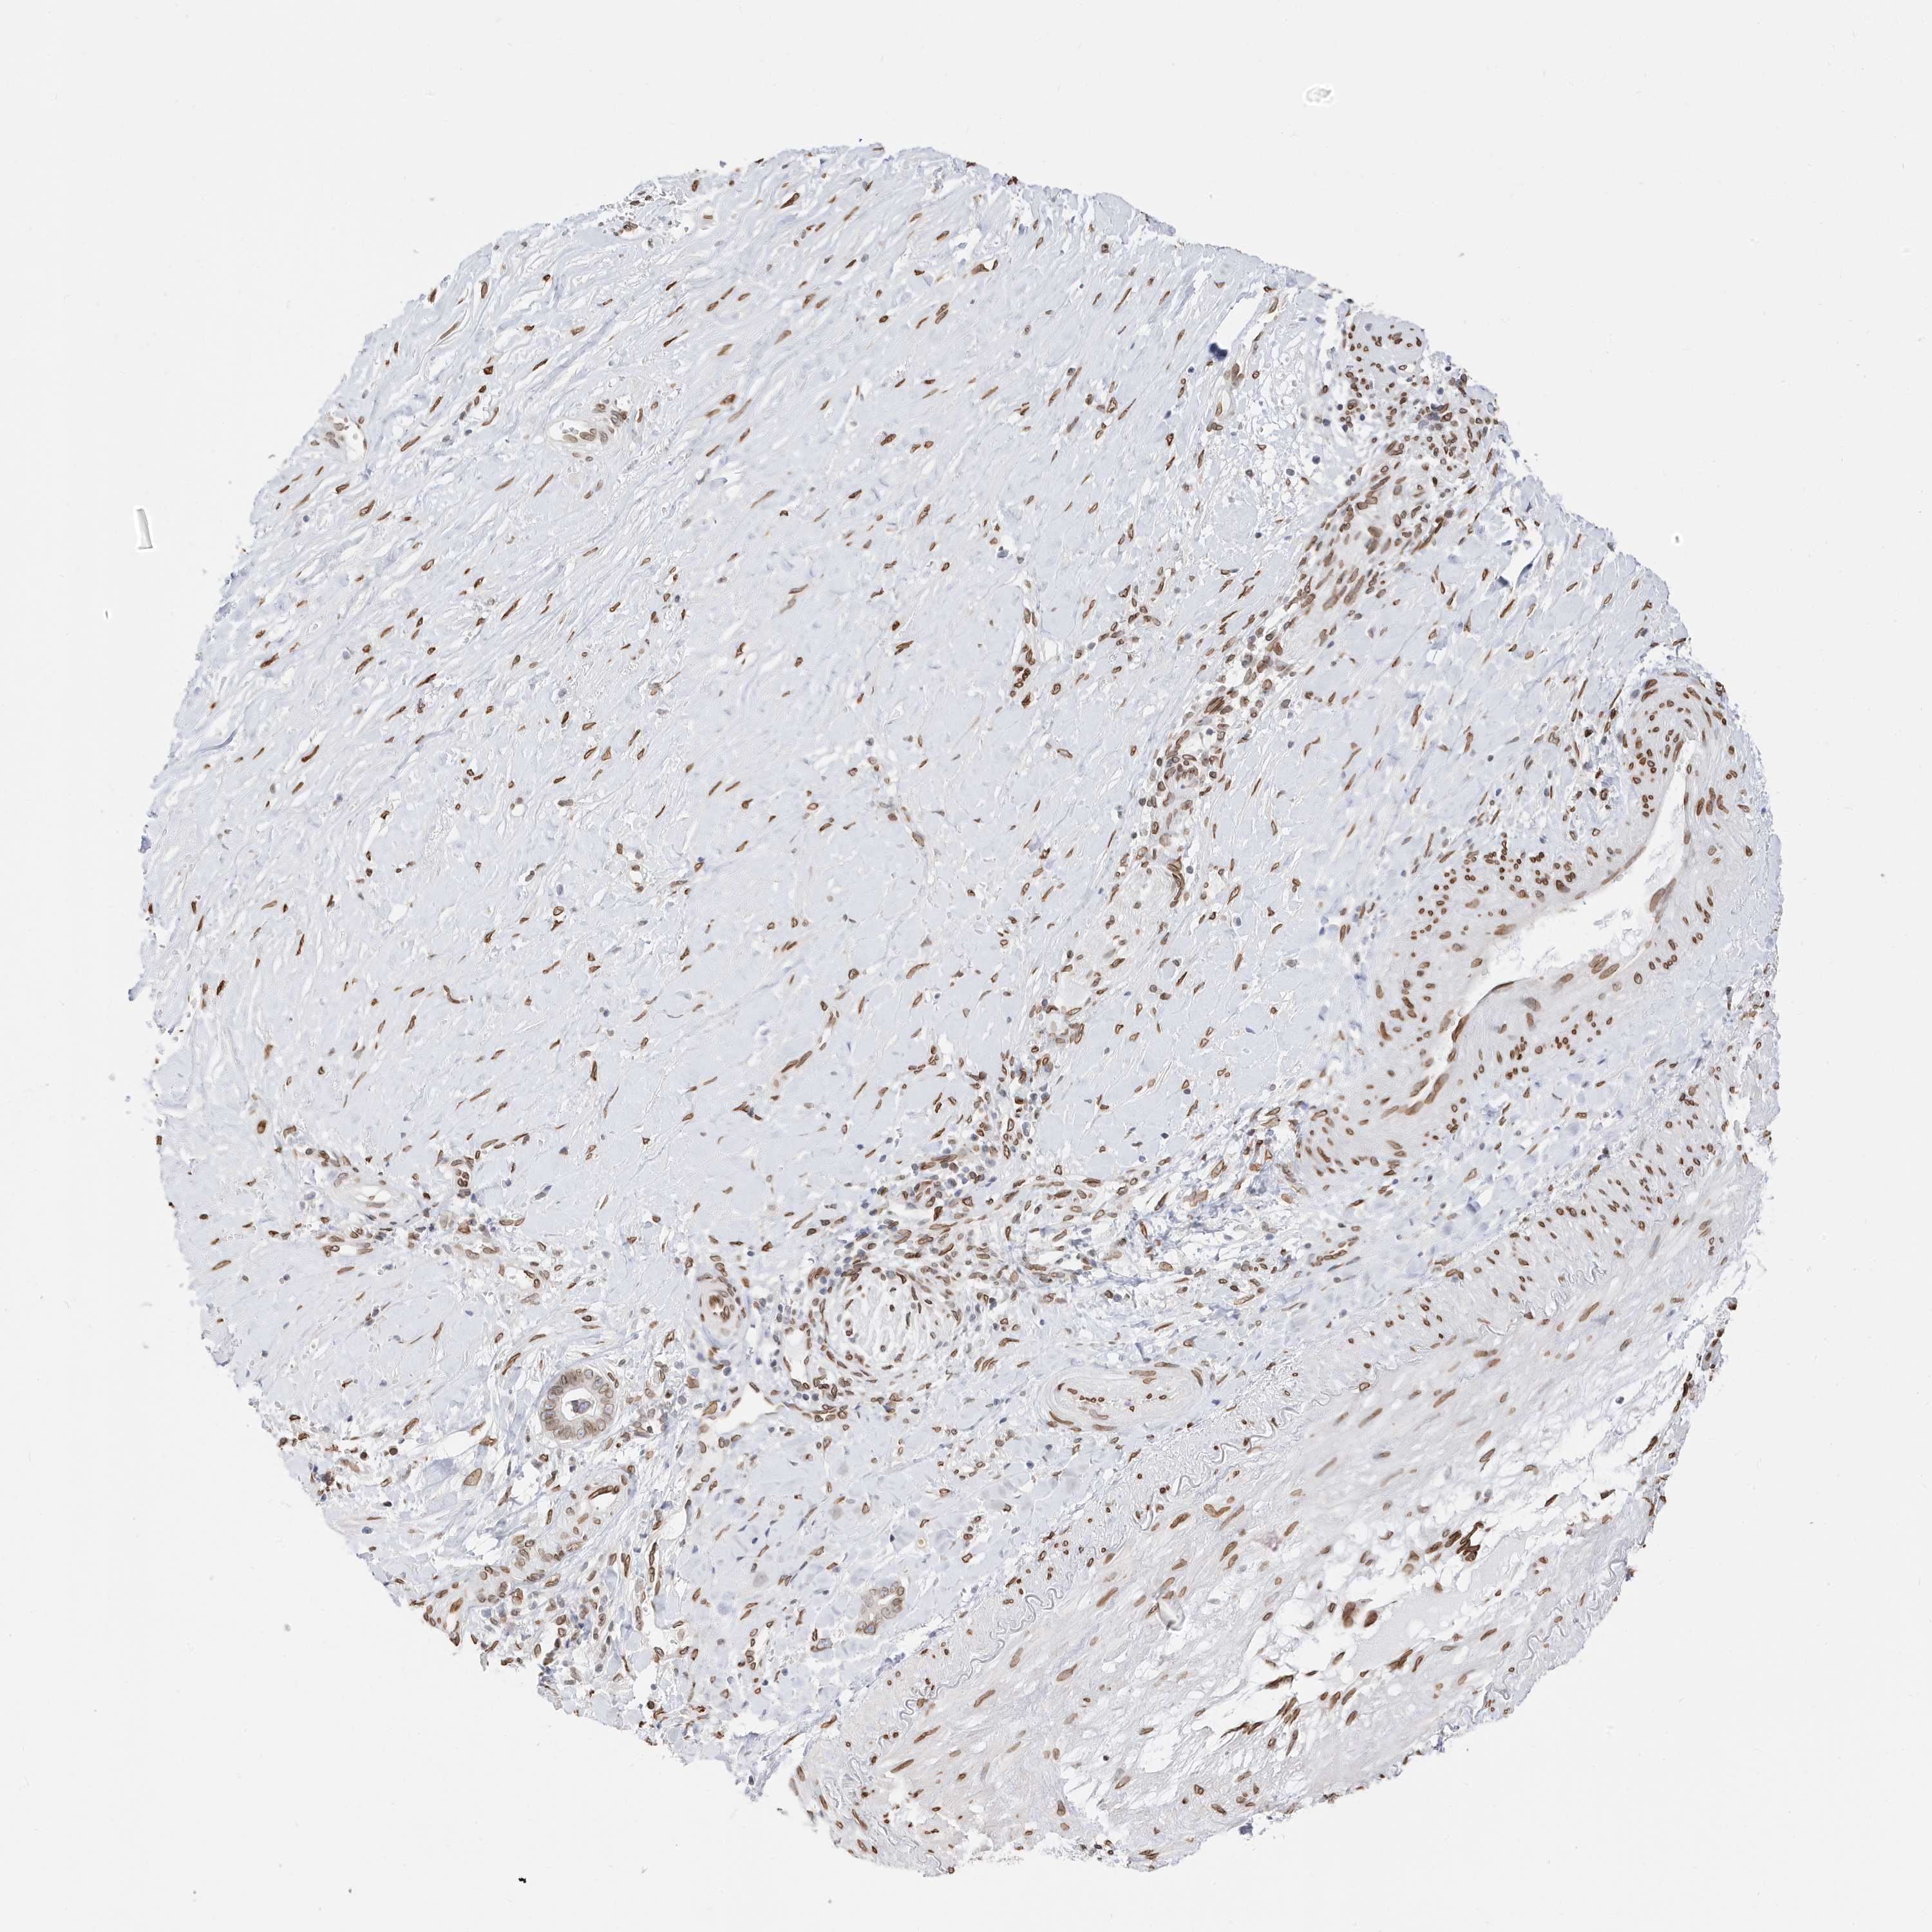

LIVER CANCER - Protein expressioni

A mouse-over function shows sample information and annotation data. Click on an image to view it in a full screen mode. Samples can be filtered based on level of antibody staining by selecting one or several of the following categories: high, medium, low and not detected. The assay and annotation is described here.

Note that samples used for immunohistochemistry by the Human Protein Atlas do not correspond to samples in the TCGA dataset.

Antibody stainingi

Antibody staining in the annotated cell types in the current human tissue is reported as not detected, low, medium, or high, based on conventional immunohistochemistry profiling in selected tissues. This score is based on the combination of the staining intensity and fraction of stained cells.

Each image is clickable and will lead to virtual microscopy that enables deeper exploration of all samples and also displays staining intensity scores, fraction scores and subcellular localization as well as patient and tissue information for each sample.

Antibody HPA029090

Staining

High

Medium

Low

Not detected

Intensity

Strong

Moderate

Weak

Negative

Quantity

>75%

75%-25%

<25%

None

Location

Nuclear

Cytoplasmic/membranous

Cytoplasmic/membranous,nuclear

Cholangiocarcinoma

Carcinoma, Hepatocellular, NOS